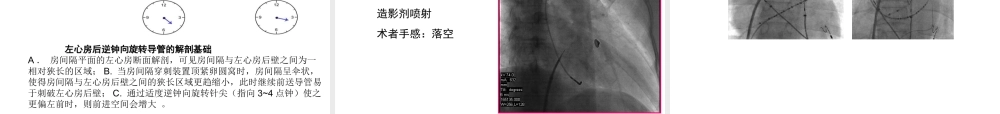

房间隔穿刺术李述峰左侧旁路房间隔途径消融。心房颤动消融。左房房性心动过速消融。左房心房扑动消融。植入左心室起搏电极建立到左房的导管通路建立到左房的导管通路房间隔穿刺意义左室有关心律失常消融的替代途径和必要补充二尖瓣球囊扩张术经皮左心耳堵闭术先天性心脏病导管介入治疗左心房-股动脉循环支持建立到左房的导管通路建立到左房的导管通路房间隔穿刺意义既往曾行房间隔缺损(金属)伞堵术既往曾行房间隔缺损补片(人造补片)手术明确的左房血栓明确的左房粘液瘤房间隔穿刺禁忌严重心脏、胸廓或脊柱畸形凝血机制严重障碍或不能耐受抗凝治疗下肢静脉、股静脉或髂静脉血栓形成下腔静脉梗阻,肿瘤压迫等血流动力学不稳定房间隔穿刺禁忌主动脉、房间隔与卵圆窝的大致界线房间隔右心面房间隔左心面房间隔解剖特征中央仅厚约1mm左右房间隔解剖特征中心窝底部很薄,此位置是房间隔穿刺进入左心房的理想部位房间隔穿刺针和鞘影像学X线RAO(45º~60º)为主X线PA确定穿入左房技术造影剂指示方法=影像学+确定穿入左心房房间隔穿刺方法学长鞘:Preface鞘管/Mullins鞘管/Swartz鞘管或其它长导丝:0.032inch/0.035inch145cm导丝BRK房间隔穿刺针(50ml)造影剂10ml注射器×21%的利多卡因配制好的5000~6000U肝素盐水房间隔穿刺器械厚度约3~4mm,其前缘对向升主动脉中央,后缘与房间沟一致房间隔平面与矢状面平均夹角45±8房间隔平面与冠状面平均夹角47±8房间隔解剖特征房间隔穿刺过程房间隔穿刺基本步骤-1后前位透视下将穿刺鞘管沿指引钢丝送至上腔静脉,之后撤出导引钢丝经鞘管送入房间隔穿刺针(距穿刺导管顶端开口1cm处,指示器指向12点钟),推注少量的造影剂2cm左右房间隔穿刺基本步骤-2房间隔穿刺基本步骤-3从上腔静脉向下回撤导管,同时顺钟向旋转使之指向左后方(4-5点)。导管缓慢回撤经过两次跳跃向左滑入卵圆窝。房间隔穿刺基本步骤-4在LAO30下将可调弯(股静脉途径)或固定弯式(上腔静脉途径)10极冠状窦电极远端置于3点位房间隔穿刺基本步骤-4A房间隔穿刺基本步骤-4RAO45°示房间隔穿刺点位于心影后缘与冠状静脉窦电极远端连线的中点,穿刺针(鞘管)远段弧形消失,呈一直线状后前先不出针,用内鞘顶住房间隔,之后出针穿刺针方向稍向前(逆钟向)房间隔穿刺基本步骤-5穿刺针微调针尖进入左心房后逆钟向旋转导管的解剖基础A.房间隔平面的左心房断面解剖,可见...